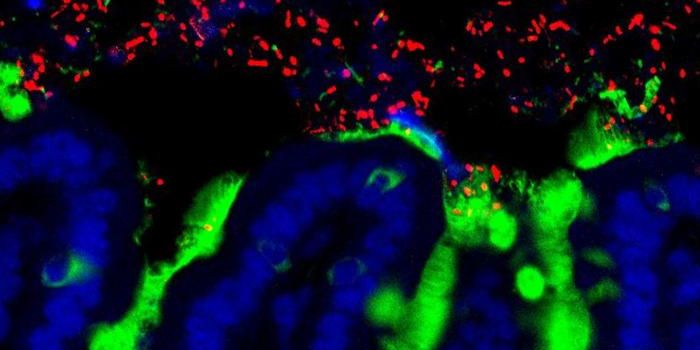

SEP 02, 2024Cell & Molecular BiologyOur skin is a crucial, protective barrier that is considered to be a major part of our immune defenses. When pathogens t ...